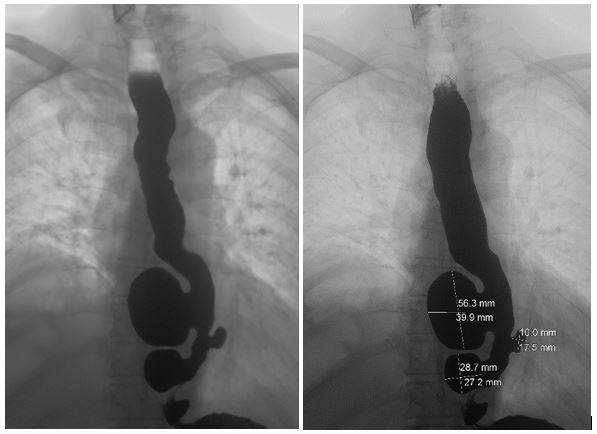

Durante la fase de recuperación clínica, se decidió actualizar el estudio mediante un esofagograma, que mostró una dilatación esofágica moderada con dificultad para la progresión del contraste hacia el estómago, así como tres divertículos epifrénicos con dimensiones de 56 mm, 17 mm y 28 mm de diámetro (Imagen 3).

Foto 3. Esofagograma baritado minutado siguiendo el protocolo de De Oliveira. Se visualizan tres divertículos esofágicos epifrénicos junto con retención de contraste en el esófago.